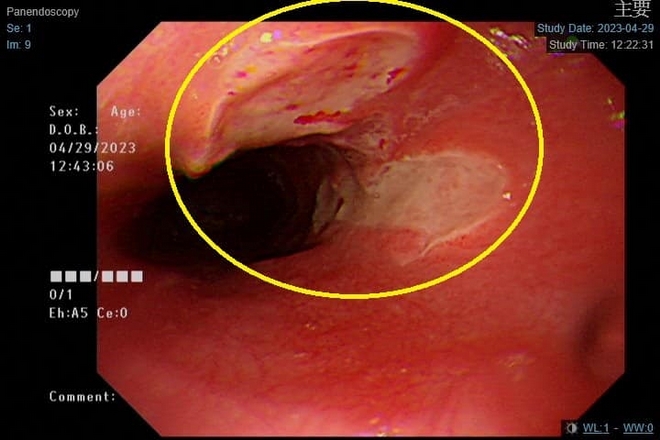

當病人因為機能、構造或心理原因,造成進食時食物不易咀嚼、吞嚥或容易嗆到,即為「吞嚥困難。馨蕙馨醫院胃腸肝膽內視鏡中心主任吳宗勤於臉書粉絲頁表示,最近有幾位年輕人胸口疼痛合併吞嚥困難來門診,經檢查後是「食道潰傷」。

患者的食道潰傷。圖片來源:吳宗勤臉書粉絲專頁

「食道潰瘍」是指食道黏膜受到破壞所造成,反覆的食道破壞,或者嚴重的食道潰瘍所產生的纖維化會造成食道狹窄。吳宗勤表示,食道潰瘍通常女性好發,大概佔了7成,好發在食道中段較狹窄的位置,而症狀也根據潰傷程度不同:

• 輕度:吞嚥固體食物時,有異物卡在中間伴有輕微疼痛。

• 重度:潰瘍較深就會引起出血,甚至喝水都會感到疼痛。